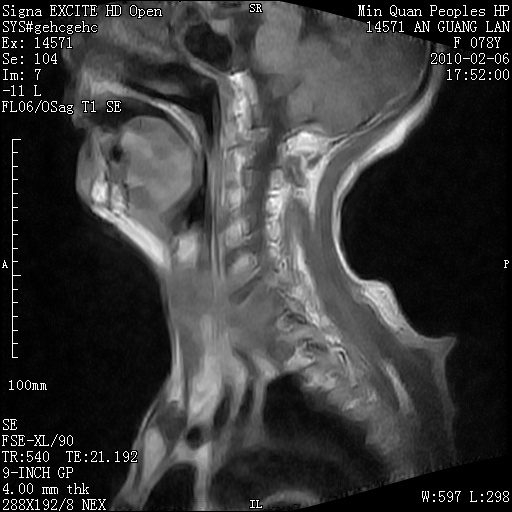

标题: MRI2763:C6、C7椎体病变性质?

f,78y,颈部与双上肢阵发性剧痛40余天。ct可见c6、c7椎体虫蚀样破坏,其间椎间隙变窄(没有图片资料可供上传)。

考虑椎体结核并椎旁脓肿。

考虑:c6/7椎体结核并椎旁脓肿形成,建议增强扫描。